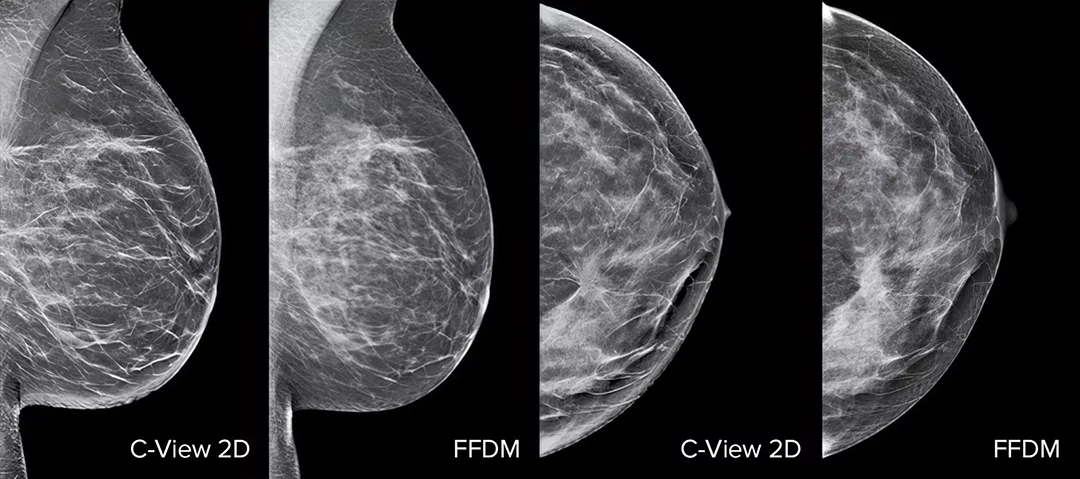

Architectural distortions, mass lesions, and bright spots commonly found in microcalcifications are more visible in the C-View 2D image than on the traditional FFDM 2D images or tomo slices.4,6-9

The Proof is in the Details

C-View 2D images are clinically proven3,5 and FDA approved to diagnostically replace the FFDM images within a tomosynthesis screening exam. The images are also a navigational aid to the tomosynthesis slice review. Published studies show that the low dose 3D Mammography exam finds invasive cancer earlier, while also reducing false positive recall rates compared to 2D alone.4,5,7

Architectural distortions, mass lesions, and bright spots commonly found in microcalcifications, are more visible in the C-View 2D image than on the traditional FFDM 2D image or tomo slice.4,6-9

Images of breast x-ray